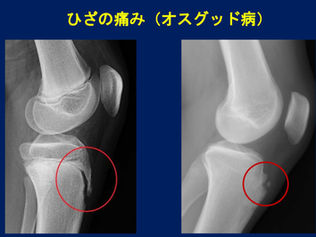

ジュニア選手のケガ予防④膝の痛み「オスグッド病」

昨年末よりブログのための時間確保が難しく更新が滞りがちです。 もし更新を楽しみにしてくださっている方がいらしたら、お待たせをして申し訳ございません。 気長にお付き合いいただければ幸いです。 さて研修会 「ジュニア期に起こりやすいケガ」...